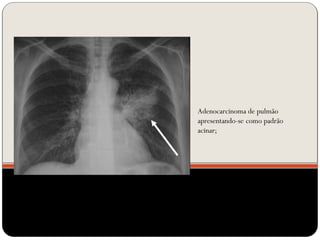

Adenocarcinoma de pulmão

apresentando-se como padrão

acinar;